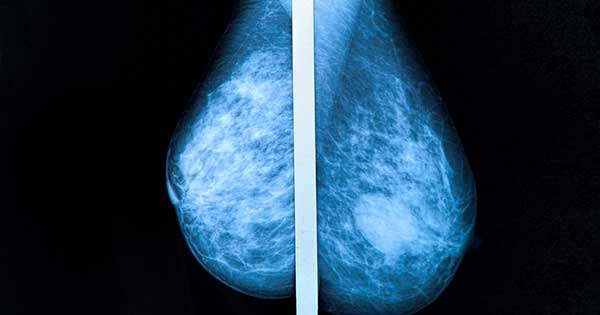

En general las mujeres jóvenes tienen mamas más densas, pero en el transcurso de la vida la densidad mamaria va disminuyendo, es decir mujeres jóvenes tienen mamas más densas que mujeres de mayor edad. La densidad mamaria puede ser comprobada mediante una mamografía, examen que se realiza como tamizaje para detectar si hay lesiones sospechosas para cáncer de mama y que se recomienda realizarlo a partir de los 40 a 50 años, según factores de riesgo y si existen antecedentes familiares de cáncer mamario.